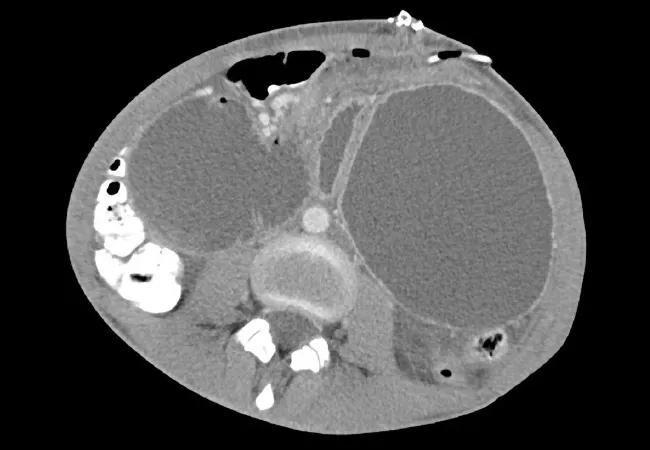

Figure 1A and 1B. CT scan of abdomen showing massively dilated, fluid-filled stomach (S) and duodenum (D). Figure 1B. The imaged portion of the distal esophagus is also fluid-filled and dilated (E). Contrast fills the jejunum and more distal small bowel, and is seen within the colon to the level of the hepatic flexure.